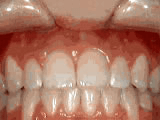

Deep overbite - Lower front teeth bite into palate

This adult patient, age 25, required braces and jaw surgery to correct his severe overbite, with treatment taking two years. His problem could have been corrected without surgery if he had been treated before he was a teenager.